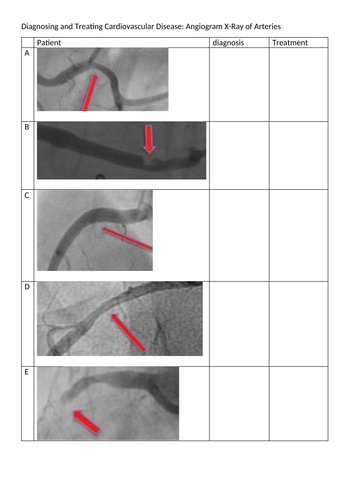

Engage pupils in Cardiovascular topic. Pupils see from Doctor’s perspective and use real examples of ECG and X-Ray to inform diagnosis and treatment suggestions.